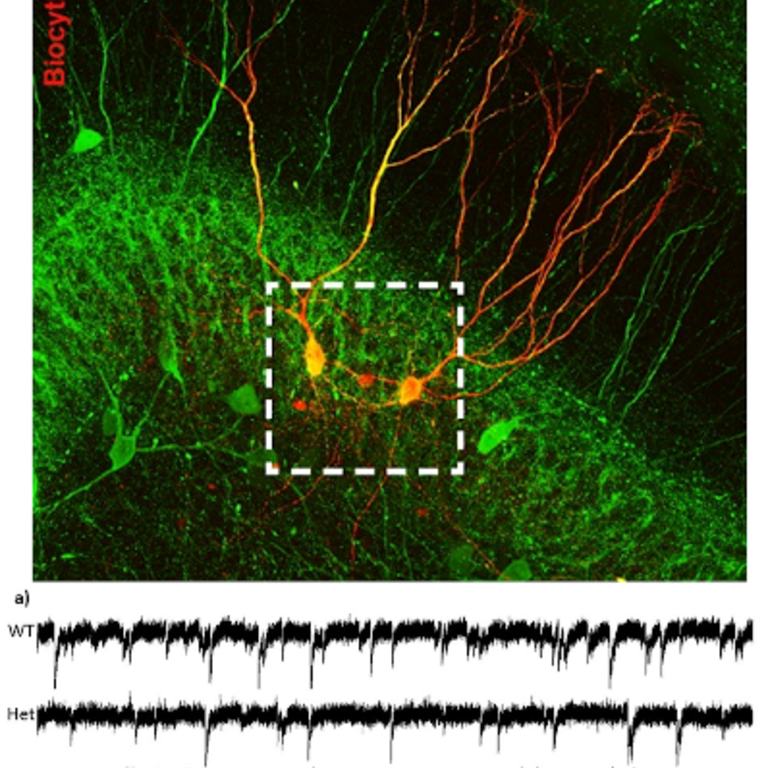

Our research focus is to determine how connectivity and modulation of inhibitory circuits shapes emergent network behavior in the normal brain and in neurological diseases. The concept that tonic inhibition, mediated by high affinity extra-synaptic receptors, is a major determinant of neuronal excitability, and that certain forms of epilepsy and ataxia are associated with alterations in tonic inhibition, has led to an increasing interest in understanding how tonic extra-synaptic inhibition is regulated. Our goal is to identify mechanisms that modulate tonic inhibition during neuronal activity and determine how these mechanisms are altered in neurological disease states. This research will identify specific perturbations in the inhibitory networks and thereby point out novel therapeutic strategies to treat these conditions. My work combines electrophysiological techniques with computational modeling of network behavior to gain an in depth understanding of the mechanisms of inhibition.